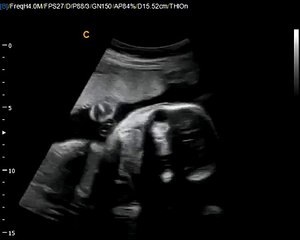

12 Weeks Pregnant Gender Determination Ultrasound

85 chance its a girl - determined at the end where the cursor is pointing\rbr\rbr*confirmed 100 at 20-week ultrasound